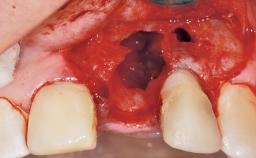

Late Placement of an Implant in a Maxillary Left Central Incisor Site

A 30-year-old female patient had lost tooth 21 and was referred to our clinic for consultation and treatment. Due to advanced apical infection, tooth 21 had been extracted two months earlier at another clinic and an acrylic-resin tooth had been bonded to the adjacent teeth. The patient desired implant treatment to avoid any damage to the adjacent natural teeth. While the patient had no history of any systemic disorder, she was a heavy smoker and exhibited medium to advanced periodontitis in the entire jaw. After the initial treatment to achieve a pocket probing depth of less than 4 mm and no bleeding on probing, a decrease in the height of the papillae mesial and distal to the extraction site and overall gingival recession were observed.

Bone Volume Deficient horizontally, requiring prior grafting